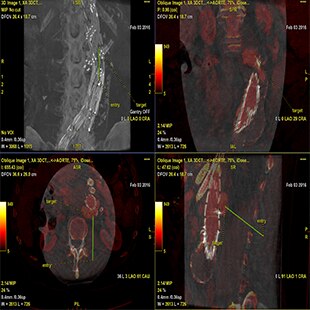

INTERVENTIONS AU NIVEAU DU RACHIS

Planifier

Guider

Évaluer